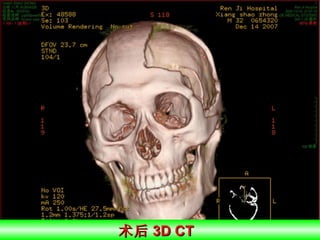

术后 3D CT